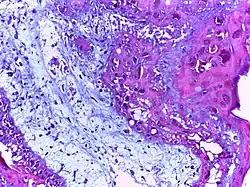

Squamous cell carcinoma of the skin | Well-differentiated squamous cell carcinoma skin showing malignant cells with mild atypia resembling normal squamous epithelial cells with intercellular bridges, individual cell keratinisation and nests of keratin pearls. | Category: Histopathology of squamous cell carcinoma of the skin | Squamous cell carcinoma |

![]() |